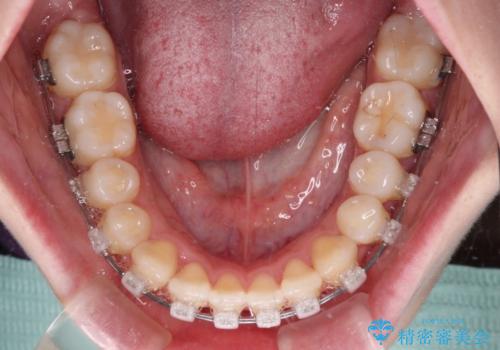

- クリアブラケット

- 2年

治療開始当初は舌の突出癖が改善されておらず、上下前歯の隙間がより顕著な状態となりました。